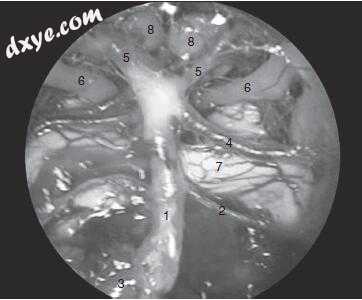

21.jpg

图-21. 在经室间隔的方法期间的手术内窥镜视图:1,基底动脉和分支; 2,小脑前下动脉; 3,椎动脉; 4,小脑上动脉; 5,大脑后动脉; 6,颅神经III号硬膜内过程; 7,脑干; 8,乳头体。